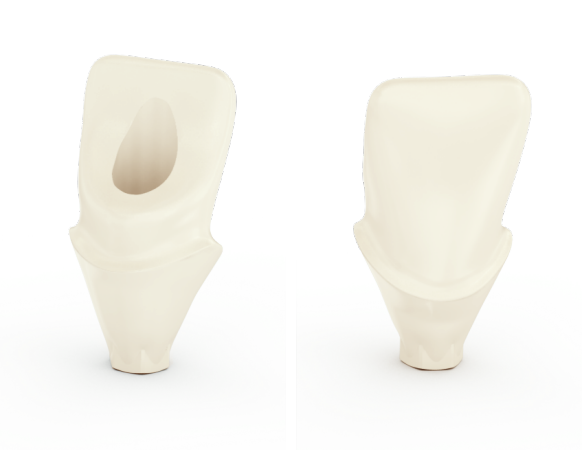

Connective Contour – increased soft tissue contact zone and volume

The unique contour that is created when you connect the abutment to the implant.